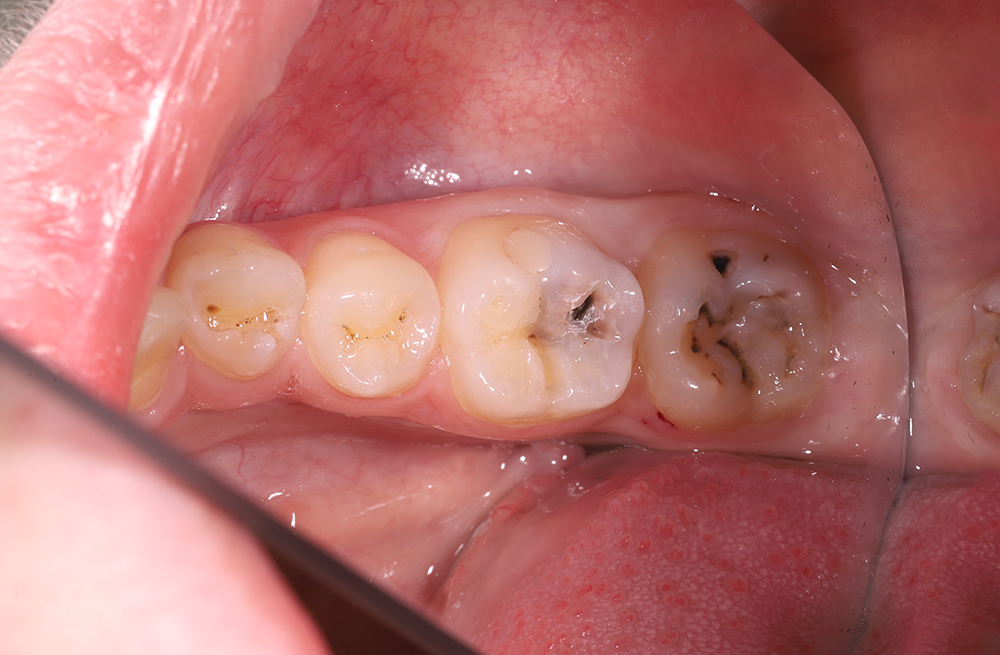

Лечение кариеса дентина композитным материалом Harmonize A3,5